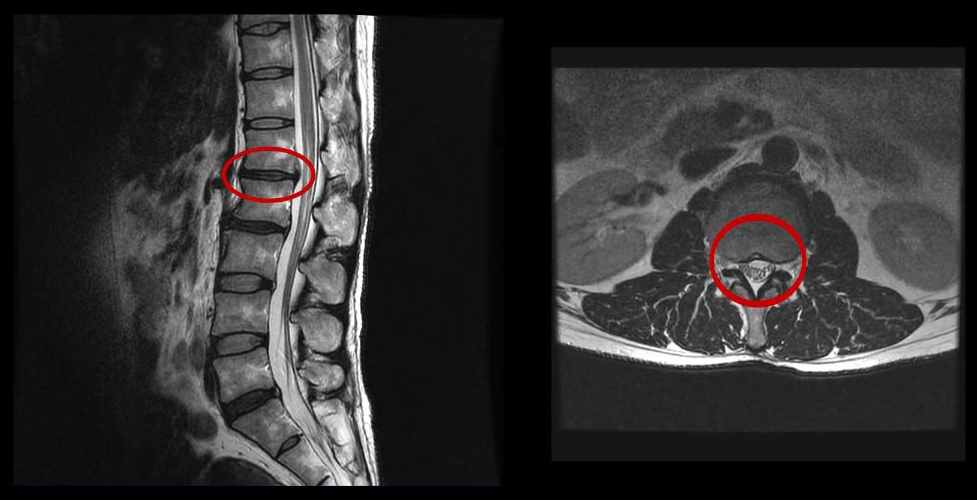

그런데 이 환자분의 MRI를 보면 여러 마디에 퇴행성디스크가 있습니다.

<2-3번>

이 환자분은 MRI상으로 거의 대부분 마디의 디스크가 퇴행되고 수핵이 밀려나와 있으며, 정상적인 허리 마디는 4-5번 하나 정도입니다. 그렇기 때문에 MRI만 보면 아마 대부분의 병원에서 허리디스크탈출 또는 퇴행성디스크로 인한 허리통증 및 다리통증으로 진단하고 치료할 것입니다. 이분도 그래서 20년간 그런 치료를 무수히 많이 받았으나 그 어떤 치료도 별 도움이 되지 않았습니다.

이 환자분처럼 오랜 기간 만성적인 허리통증이 있고, 엉덩이가 저리면서 심지어는 양쪽 다리저림까지 있는 환자분들이 많습니다. 그런데 이 환자분의 MRI를 보면 여러 마디의 퇴행성디스크, 디스크탈출, 황색인대의 두꺼워짐, 후관절의 퇴행 등 다양한 병변들을 가지고 있는 걸 볼 수 있는데요. 그렇기 때문에 많은 병원에서 이분을 디스크로 진단하고 거기에 따른 치료가 이루어졌습니다. 그러나 저희가 보기에는 이분의 MRI상으로 보이는 여러 마디의 디스크 문제가 이 환자분이 갖고 있는 증상을 설명할 수 없었습니다.